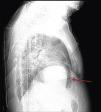

A 84‐year‐old woman was referred to our emergency department from another hospital with acute dyspnea at rest and hypoxemia. On admission a peripheral venous catheter had been inserted for fluid replacement and she had undergone computed tomography pulmonary angiography (CTPA) for suspected pulmonary embolism. Soon after the exam the patient became confused and drowsy and her respiratory failure worsened significantly without hemodynamic instability. CTPA confirmed the presence of bilateral central and peripheral thrombus and a large amount of air in the brachiocephalic veins, pulmonary artery (Figure 1) and right ventricle (Figures 2 and 3). She was considered to have VAE unrelated to the administration of contrast, given a topogram image that suggested the presence of air in the right ventricle before contrast injection (Figure 4). It was therefore assumed that the VAE resulted from the placement or manipulation of the peripheral venous catheter previously inserted in another institution. The patient was immediately given normal saline, a Hudson mask was applied and she was placed in left lateral decubitus position (Durant's maneuver) and in the Trendelenburg position, to keep the right ventricular outflow tract lower than the right ventricular cavity causing the air to migrate upwards, minimizing the likelihood of embolism. Her clinical status improved rapidly and she recovered without sequelae. Bedside transthoracic echocardiography showed no acute ventricular dilation or dysfunction, and the patient was transferred to another hospital for hyperbaric oxygen therapy.